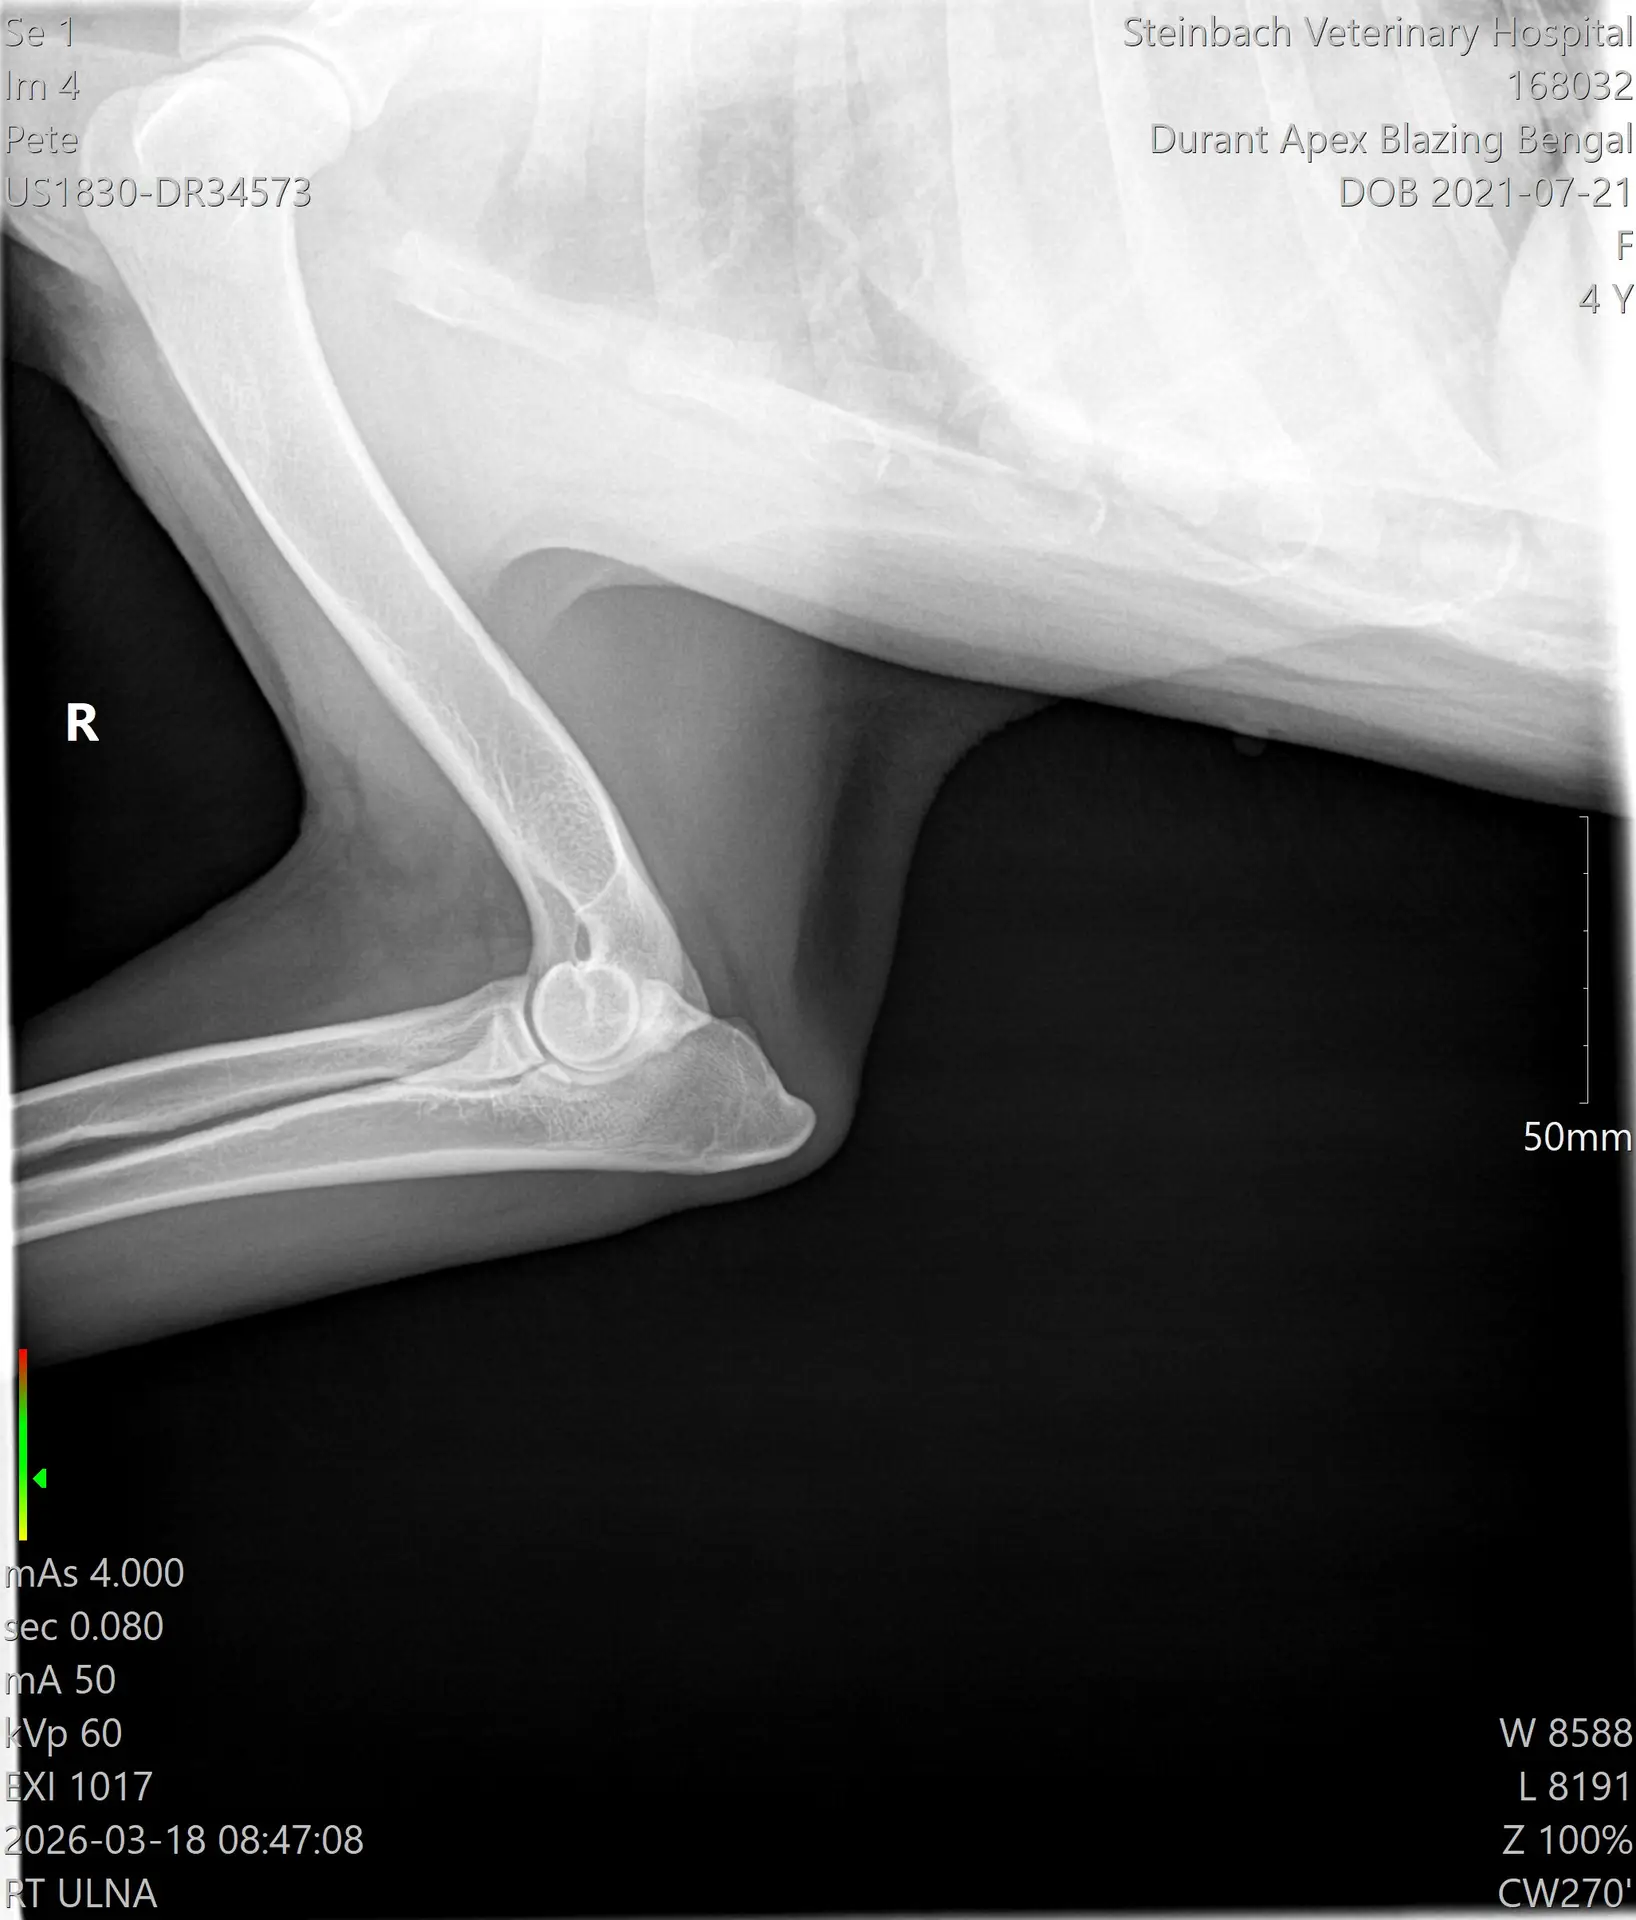

Apexx Blazing Bengal — OFA Elbow Evaluation. Excellent result. Steinbach Veterinary Hospital, March 2026.